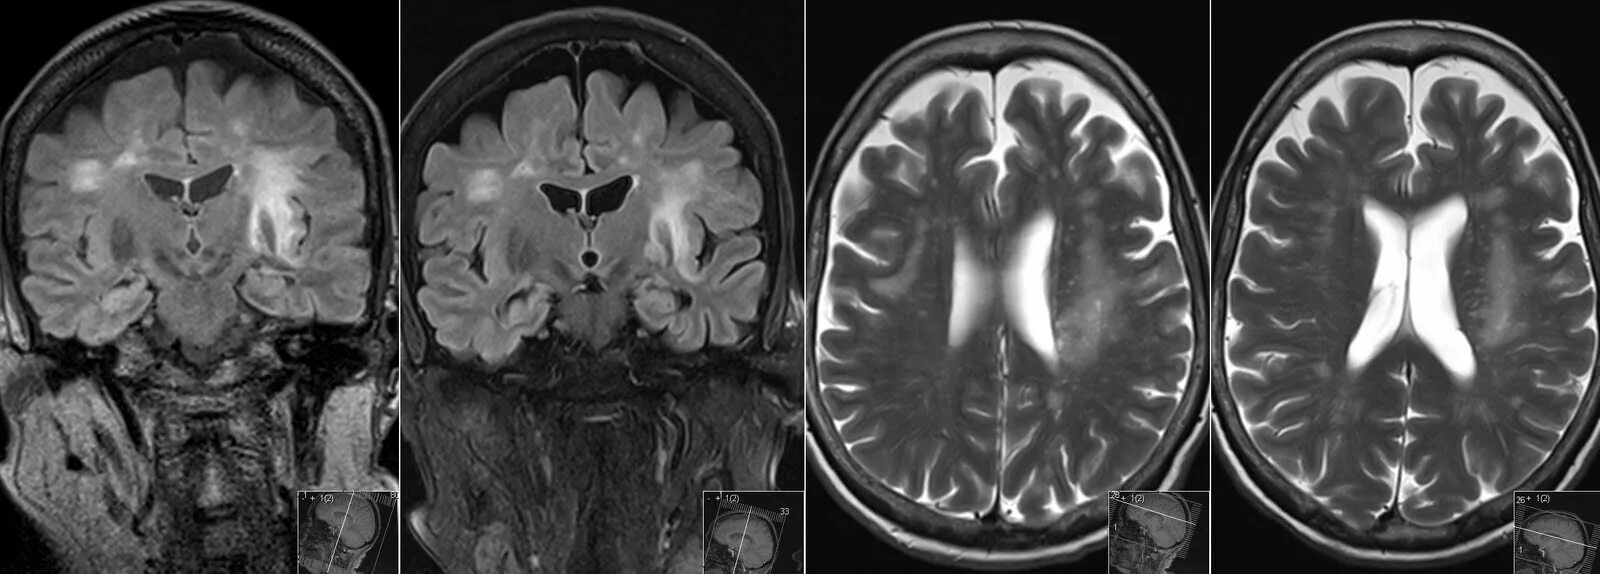

Прогрессирующее заболевание мозга